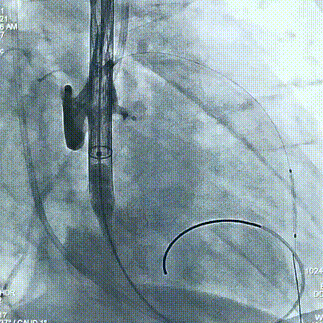

术中操作

球囊预扩

瓣膜定位

经评估后植入左主干烟囱支架